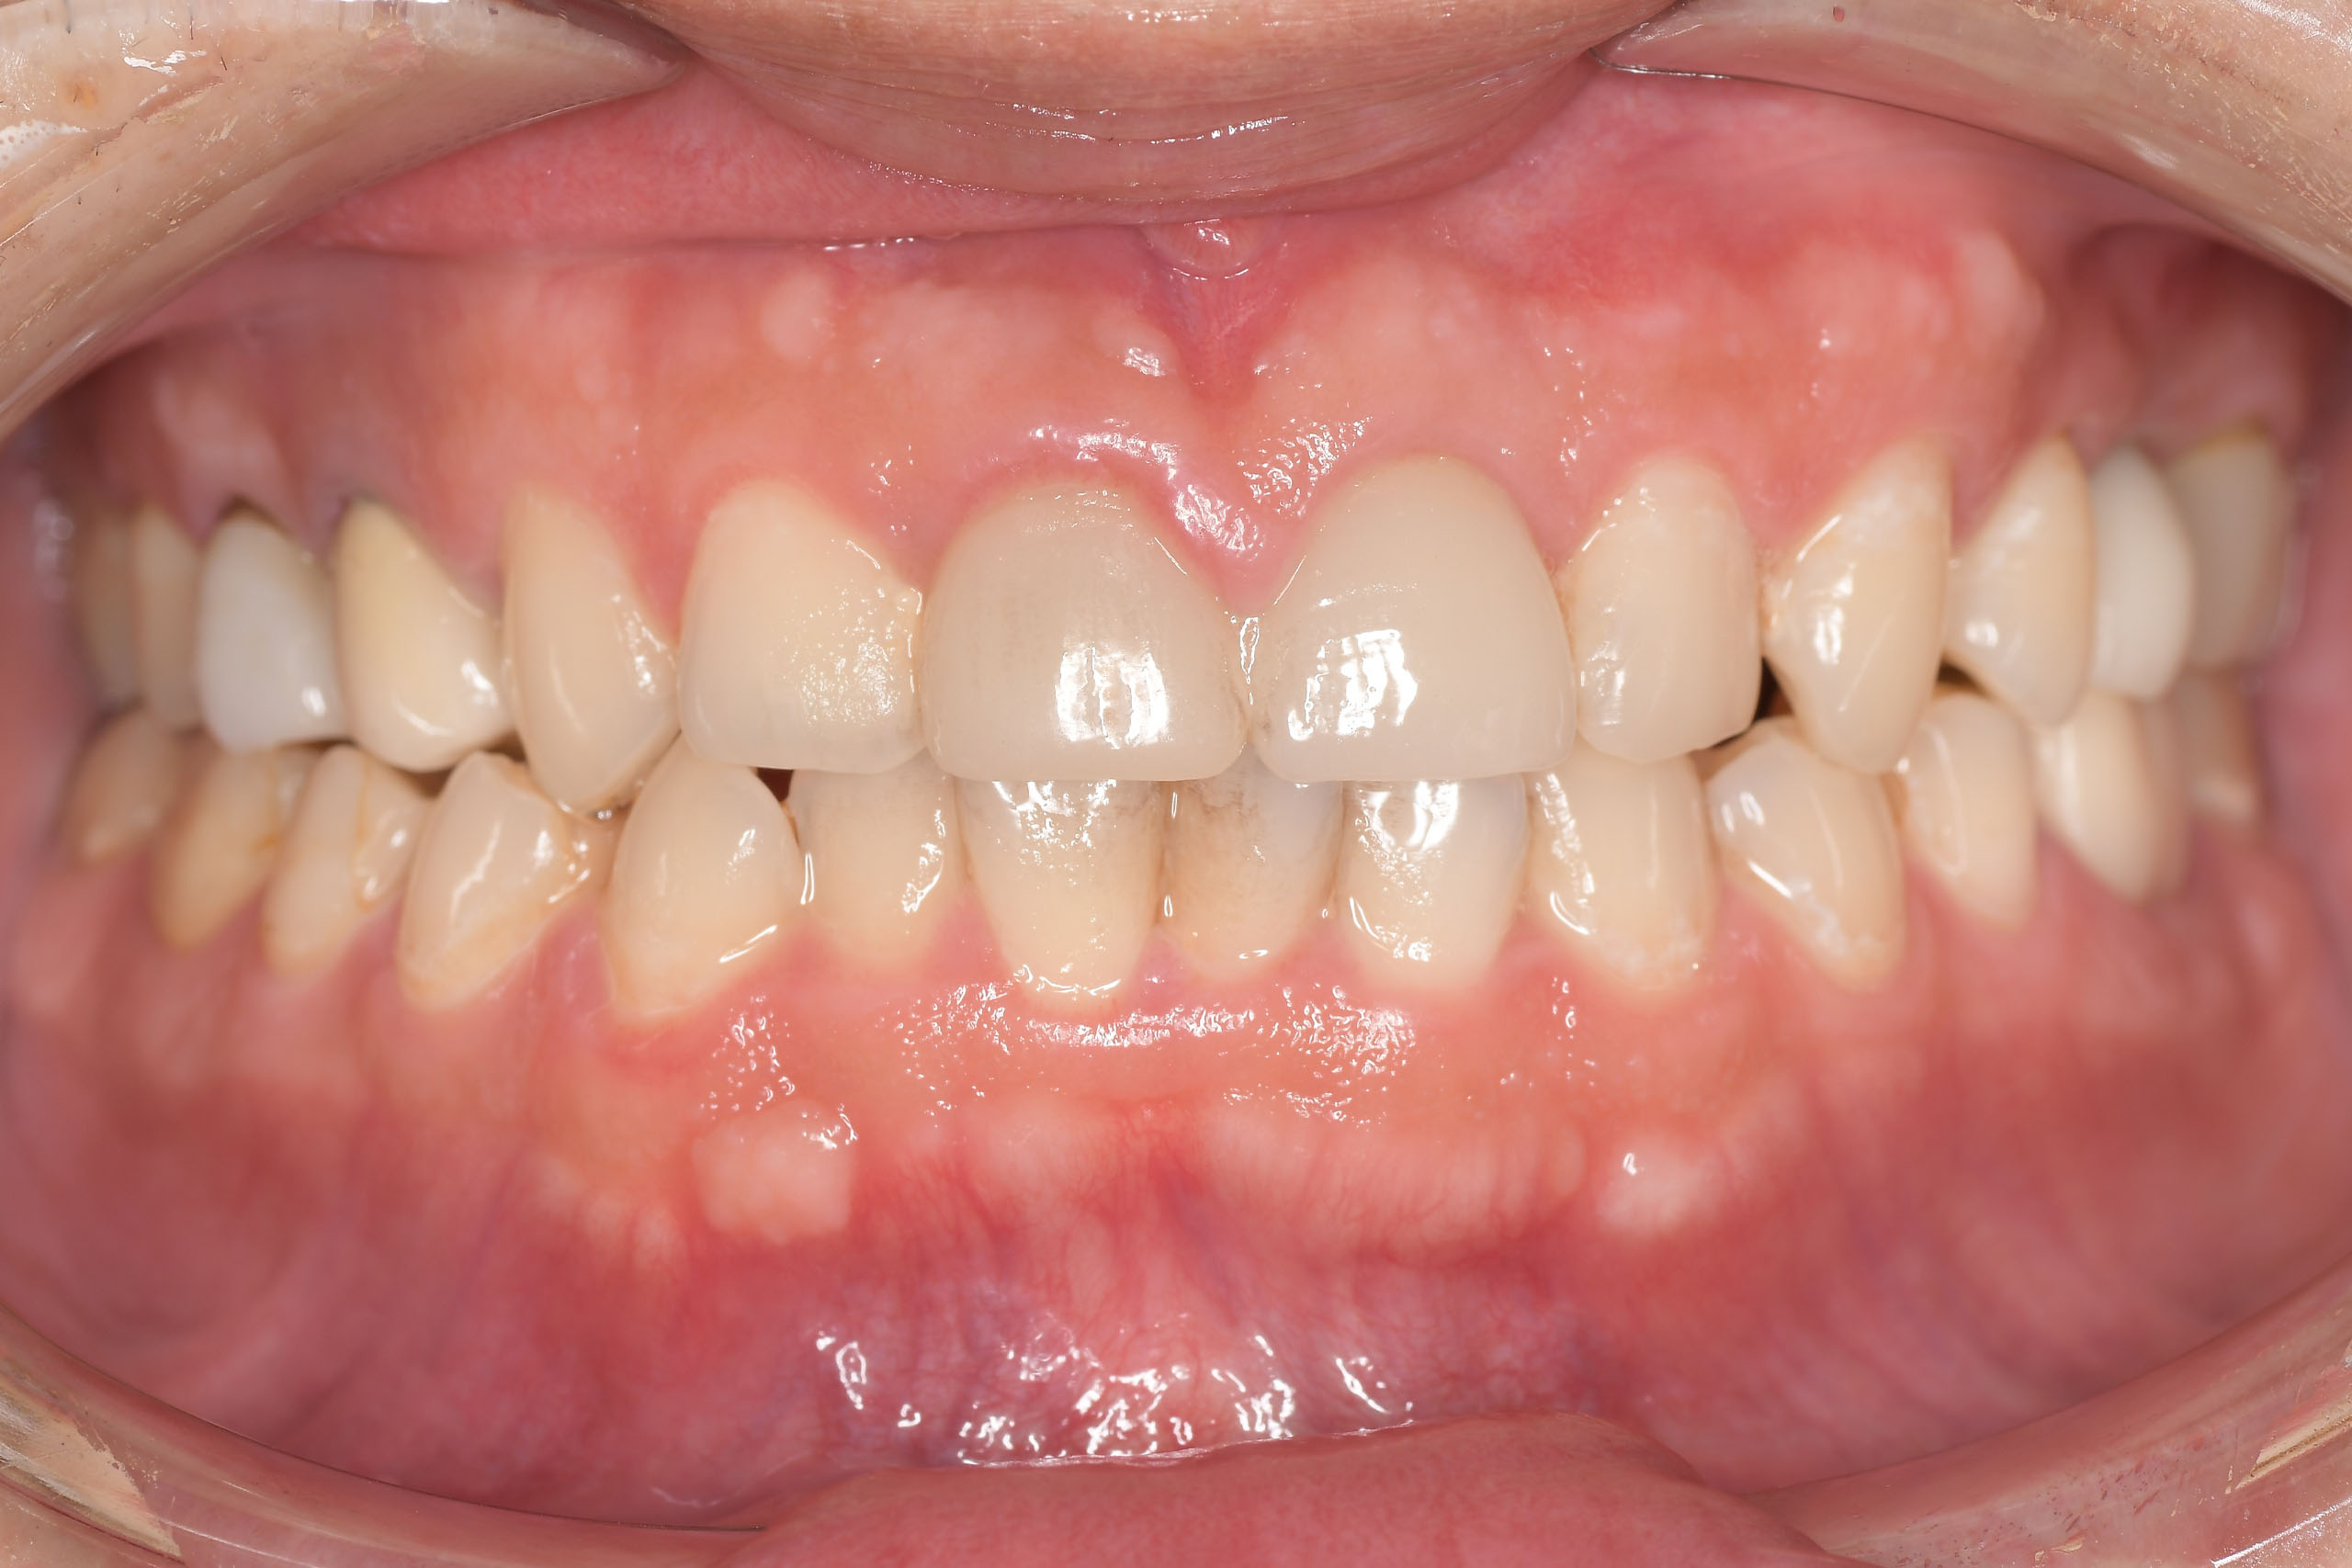

Before

After

| 主訴 | 見た目をきれいにしたい |

| 治療期間 | 6ヶ月 |

| 治療費 | ジルコニアボンド(セラミックの被せもの)¥165,000×7(税込み) オフィスホワイトニング4回 ¥4,400×4(税込み) ホームホワイトニング¥11,000 |

| リスク・副作用 | かみ合わせがとても強い方の場合、稀に割れてしまうことがあります。 |

| 先生からの提案 | 上の前歯6本と右下の2番目の歯はセラミックの被せもので治療。 残りの下の前歯5本はプラスチックの材料で虫歯を治療し、 ホワイトニングをおこないました。白くなったご自身の歯の色に合わせてセラミックの 被せものを作成しています。 模型上で完成後をシュミレーションし、上の歯茎の位置をきれいに見えるように 揃えています。(外科処置はしていません) |